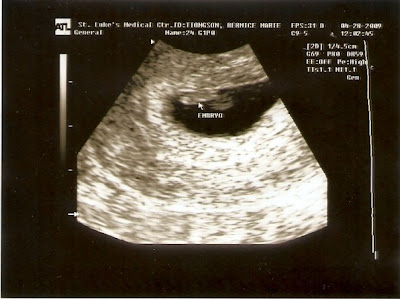

But out of love I gathered enough excitement to go with the Tiongsons to get Bern's ultrasound (13 weeks) at this neat place called In My Womb in Megamall. It's this neat little ultrasound place that's cheaper than the hospital, and it's still done by a real doctor. The best thing about it is that there's a viewing room for the family with up to five chairs. There's a huge flat screen TV on the wall so you can all see the ultrasound images and surround sound speakers! And that's probably the only reason why I got to tag along with the whole family for this intimate moment. Haha, adopted daughter na talaga!

And you know what? It was amaaaazing! Seeing that little baby squirming and kicking and turning - all inside Bern's belly! I know I've seen it on TV and my parents and titas all talk about it. But it's just really different when it's someone your age, and someone you were silly college girls with.

The most amazing things was when the doctor turned on the sound so we could hear the baby's heartbeat. Before that, the whole family and myself were soooo noisy inside the observation room. But when the doctor switched on the speakers and we could hear the baby's strong heartbeat in surround sound, everyone just grew quiet! Blanche and I slowly turned to each other and we both had tears welling up in our eyes. It was just so.. well somewhere halfway between scary and amazing. I mean, that's a real person!

And of course Bern had tears welling in her eyes too when the doctor said she was gonna have a baby girl :-) But the doctor also said to wait a few more weeks for her next ultrasound to know for sure what the gender is, coz it's kinda too soon to know for sure. So 'til then, we'll probably hold off on all the shopping for pink baby stuff.

PS - one last thing.. Don't go for the 4D imaging until your super close to giving birth na. Bern was on her third trimester and the doctor showed us the 4D image, it was still kinda scary! I could hear her say "Doc, go back to 2D nalang!" Heheh, so I guess it'll be a few more months before they go fr the 4D again.